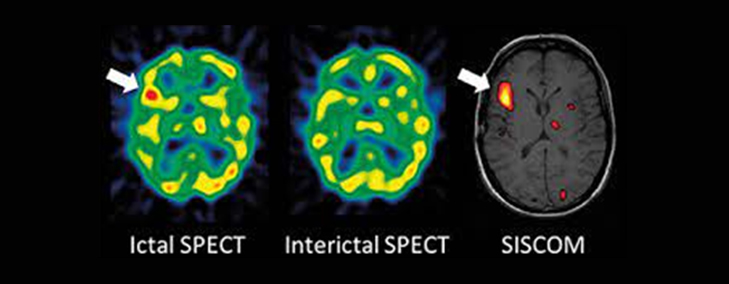

SISCOM is an acronym for “Subtraction Ictal-Interictal SPECT co-registered to MRI”. It is an imaging done in patients with refractory epilepsy planned for surgery.

SISCOM requires the acquisition of 3 scans, which are an MRI scan, an ictal SPECT scan and interictal SPECT scan.

An interictal SPECT scan involves injection of a radiotracer that gives information about the blood flow to the brain. An image is acquired using a gamma camera 1-4 hours after injection when the patient is seizure free.

An ictal SPECT involves injection of the same radiotracer as an interictal SPECT with the difference that the injection is done when the patient is having a seizure.

Together, these three images are processed in a computer and the resultant findings can help localize the possible source of epilepsy in the patient.